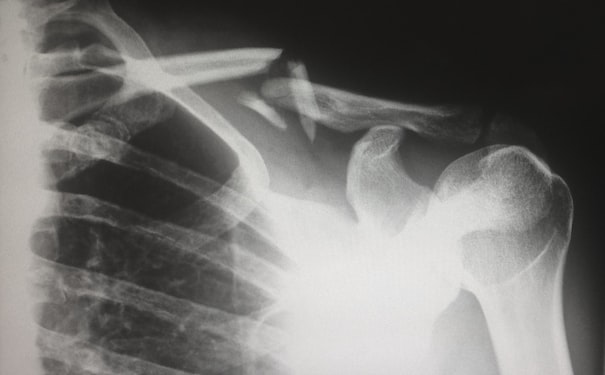

醫(yī)學(xué)模型3D建模軟件可以創(chuàng)建各種類型的醫(yī)療模型,如骨骼、器官和血管等。這些模型有助于醫(yī)生更好地理解人體結(jié)構(gòu)和功能,以便針對(duì)疾病進(jìn)行更準(zhǔn)確的診斷和治療。例如,通過在3D模型上標(biāo)記病變區(qū)域,醫(yī)生可以更容易地規(guī)劃手術(shù)和治療方案。